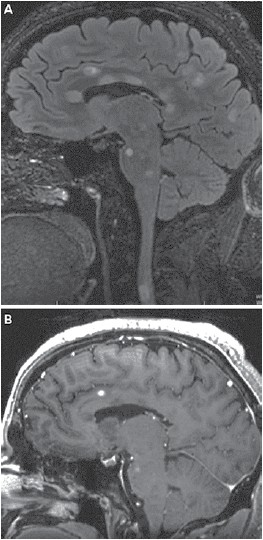

Masculino, 18 anos, sem antecedentes, foi admitido no hospital com quadro de hemiparesia à esquerda e incoordenação de início há uma semana e não progressiva. Ao exame apresenta nistagmo horizontal bilateral, hemiparesia braquio-crural à esquerda com liberação piramidal e dismetria em membros superiores bilateralmente. Realizou ressonância magnética de encéfalo que se encontra a seguir. Líquor apresenta 10 células, 94% de linfócitos, 48 mg/dL de proteínorraquia e presença de bandas oligoclonais. Paciente recebeu pulsoterapia com dose adequada de corticoide com melhora dos sintomas. Assinale a alternativa que apresenta, correta e respectivamente, o diagnóstico deste paciente e, com base neste quadro clínico, a melhor opção terapêutica inicial para ele.